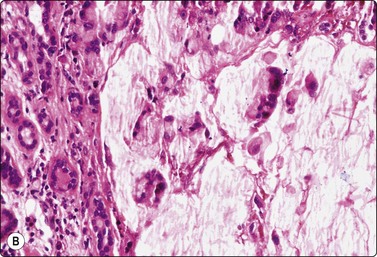

Basaloid squamous carcinoma (Fig. 4.7) is a rare distinct variant of squamous cell carcinoma of the head and neck, which is clinically aggressive and has a predilection for the hypopharynx and the tongue. The smear findings are of squamous cell carcinoma without specific features, but a predominance of basal cells may make the distinction from the solid variant of adenoid cystic carcinoma difficult.43

image

Fig. 4.7 Basaloid squamous cell carcinoma of head and neck

(A) Poorly differentiated cells with squamous features (MGG, HP; (B) Tissue section mimicking adenoid cystic carcinoma (H&E, IP).